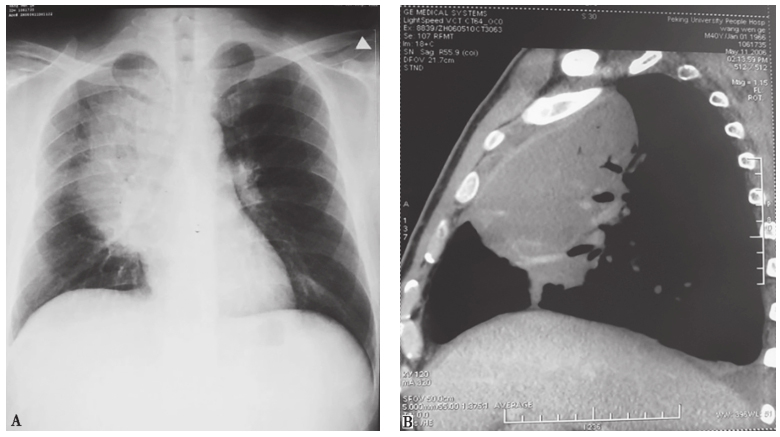

图5 肺淋巴瘤胸部影像学表现

男性患者,44岁,间断发热9个月,痰中带血1个月。胸部X线片(A)可见右中上纵隔旁肺野大片高密度影,CT(B)可见右上叶前段和中叶大片实变影,并见支气管充气征。病理诊断为肺淋巴瘤

图7 Mendelson综合征X线胸片表现

男性患者,72岁,脑梗死后发生呕吐、呼吸窘迫,伴Ⅰ型呼吸衰竭,X线胸片可见双肺弥漫高密度影(A),经糖皮质激素治疗5天后,肺内病变明显吸收(B)